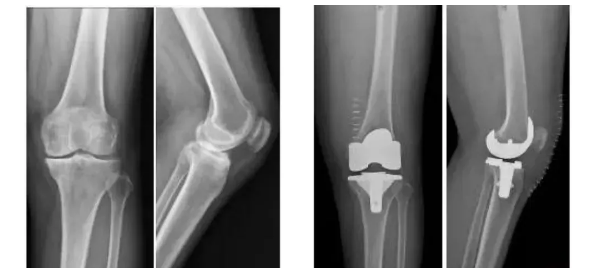

3D打印生物型人工膝關(guān)節(jié)在國內(nèi)成功植入!

膝關(guān)節(jié)骨關(guān)節(jié)炎是一種退行性疾病,近年隨著經(jīng)濟發(fā)展和人口老齡化趨勢日趨明顯,尤其是在中老年群體發(fā)病率較高,因此膝關(guān)節(jié)置換術(shù)需求量日益增長。此外,隨著居民生活水平的提高,大多患者對于膝關(guān)節(jié)置換術(shù)術(shù)后的生活質(zhì)量和植入假體有了更高的要求,隨之假體在設(shè)計和創(chuàng)新方面也更精準、更便捷化。全球shou款3D打印分區(qū)骨小梁生物型膝關(guān)節(jié)假體正是在這種高需求與高期待的新形勢下應(yīng)運而生。

目前臨床上使用的膝關(guān)節(jié)假體多為骨水泥固定型假體,骨水泥即骨粘固劑,它可以將膝關(guān)節(jié)假體固定在骨界面上。骨水泥固定存在一定局限,如骨水泥單體具有一定的毒性;與骨接觸面的骨溶解問題;隨著時間推移,會發(fā)生變形和退變等。

本次植入的生物型膝關(guān)節(jié)假體在術(shù)中無需使用骨水泥,通過機械方式進行固定,即假體與骨組織的緊密結(jié)合,獲得假體的初始穩(wěn)定性,遠期骨組織長入假體表面的微孔內(nèi)部,實現(xiàn)由機械固定向生物.內(nèi)鎖固定的轉(zhuǎn)化,zui終經(jīng)過骨整合作用獲得良好固定,預(yù)期能夠獲得更長的假體壽命。此外,生物型膝關(guān)節(jié)假體避兔了骨水泥相關(guān)并發(fā)癥的發(fā)生,縮短了手術(shù)時間,zui大程度保留了骨組織。因而減輕了患者術(shù)后疼痛,降低了圍術(shù)期并發(fā)癥發(fā)生率,有利于患者術(shù)后快速康復(fù)。

周宗科教授介紹說,該款3D打印分區(qū)骨小梁生物型膝關(guān)節(jié)假體有三個亮點,一是脛骨平臺假體采用了3D打印骨小梁分區(qū)技術(shù),三分區(qū)設(shè)計使宿主骨均勻骨長入,避免因應(yīng)力分布不均而造成平臺假體松動等問題;二是所用股骨髁假體表面為真空等離子噴涂純鈦涂層,其粗糙的接觸面增加了骨誘導(dǎo)的能力,具有優(yōu)異的即刻穩(wěn)定和長期穩(wěn)定性;三是所用平臺墊為添加維生素E的高交聯(lián)超高分子量聚乙烯材質(zhì),具有優(yōu)異的耐磨性能。